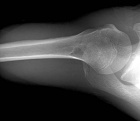

14 year old male with right shoulder pain x 1 year after a fall off a dirt-bike and multiple wrestling / sports injuries.

Zoom image: Radiological image Radiological image.